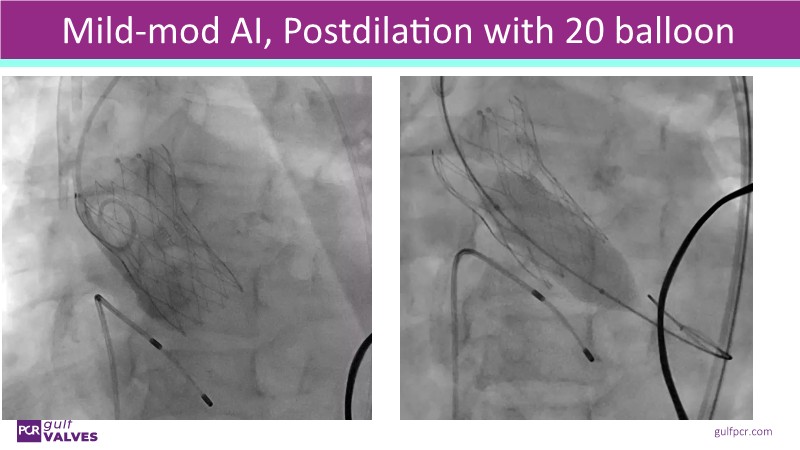

Discover a selection of cases showcasing the key features of the Navitor Valve System and its clinical applications. This session explores auxiliary access, the use of Navitor in alternative access and complex PCI, its performance in challenging peripheral anatomies, and innovative outcomes with the Vantage 30D system.